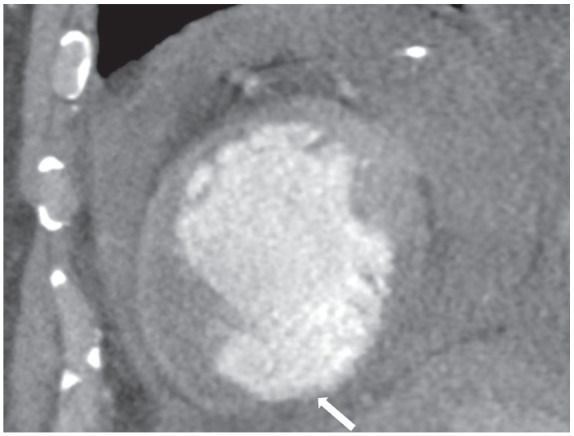

假性动脉瘤是心肌梗死(MI)的一种罕见但致命的并发症。随着心血管疾病检测和治疗技术的进步,心肌梗死后致命的结构性并发症现在已经很少见了。一旦发生,先进的诊断方法可用于早期诊断,帮助制定手术计划并改善预后。在我们的病例中,心脏计算机断层扫描血管造影术(CCTA)诊断出了心肌梗死后左心室假性动脉瘤并发血心包。CCTA 的衰减测量有助于诊断血心包的活动性外渗。该病例强调了对心肌梗死后罕见但致命的并发症需要高度怀疑,以及 CCTA 在治疗中的作用。

Pseudoaneurysm is a rare but fatal complication of myocardial infarction (MI). With the advances in cardiovascular disease detection and treatments, fatal structural complications post-MI are now rare. When they occur, advanced diagnostic modalities can be used for early diagnosis, aiding surgical planning, and improving prognosis. In our case, post-MI left ventricle pseudoaneurysm complicated by hemopericardium was diagnosed using cardiac computed tomography angiography (CCTA). Use of attenuation measurement on CCTA helped diagnose active extravasation into the hemopericardium. This case highlights the high index of suspicion needed for rare but fatal complications post-MI and the utility of CCTA in their management.